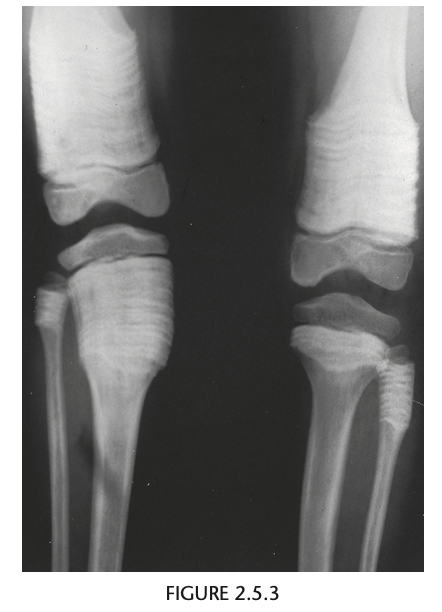

Q

Radiographs of the knees show splaying of the metaphyses and alternating radiolucent bands in the distal

femurs and proximal tibias and fibulas bilaterally. (Erlenmyer flask)

Diagnosis: Osteopetrosis

Defect in osteoclastic resorption.

Precocious (AR Lethal) and Delayed (AD asymptomatic)

Generalized osteosclerosis and diffuse cortical thick-

ening with narrowing of the medullary cavity.